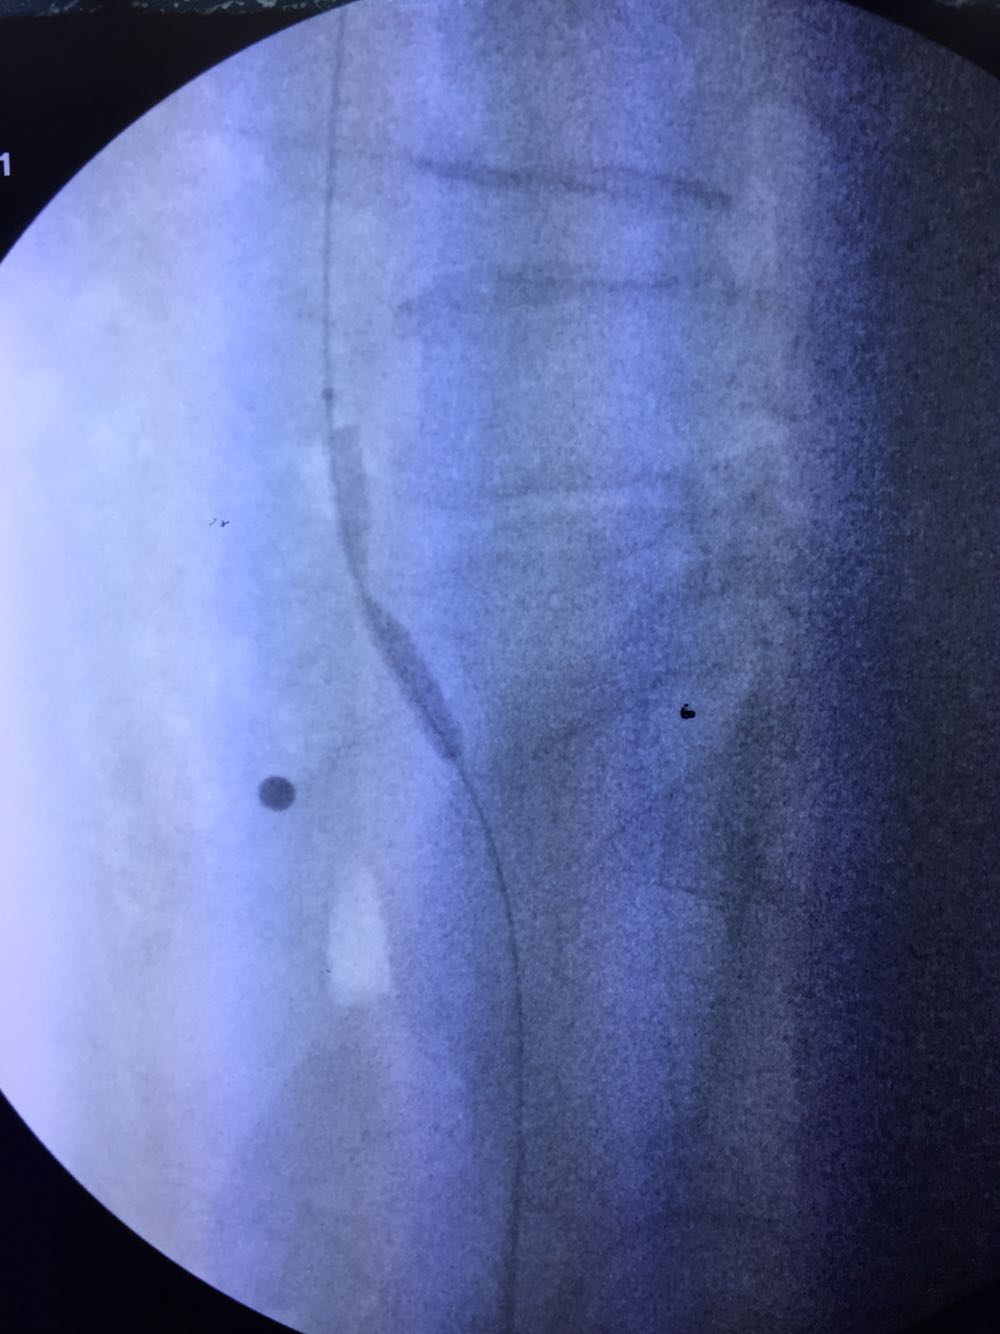

初步诊断为左下肢静脉曲张C5期,造影提示髂静脉压迫,顺行穿刺,左髂静脉球囊扩张,植入静脉支架wallstent

部分下肢静脉曲张由髂静脉压迫引起,术前需重视筛查!目前髂静脉压迫多采用腔内治疗,wallstent作为目前唯一静脉专用支架,远期通畅率良好,术后常规抗凝6-12个月